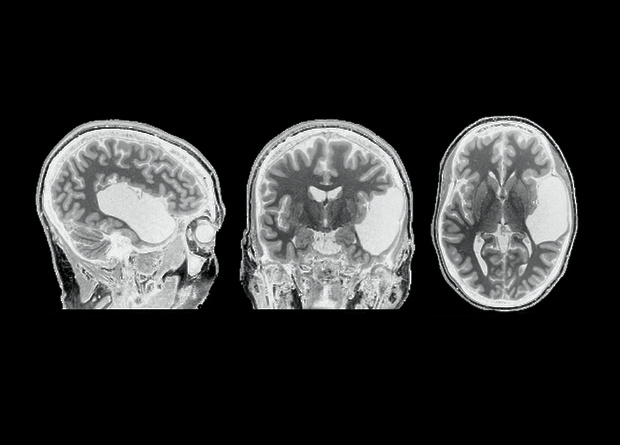

Наличие височной доли — обязательное условие для обработки языка лобной долей и, как следствие, — для появления языка в полушарии вообще. К такому выводу пришли американские ученые, которые изучили мозг женщины, в раннем возрасте утратившей височную долю левого полушария. Всю обработку языка на себя взяло правое полушарие, а вот в левом полушарии речь не обрабатывалась вообще — даже в лобной доли, которая осталась цела и выполняла другие функции, пишут ученые в журнале Neuropsychologia.

Чтобы ответить на этот вопрос, Эвелина Федоренко (Evelina Fedorenko) из Массачусетского технологического института вместе с коллегами изучила мозг женщины, которая живет без височной доли левого полушария головного мозга всю свою жизнь. Предположительно, ЕГ (так называют участницу исследования в статье) перенесла инсульт еще до рождения, но на ее развитии это не сказалось: у нее есть ученая степень, а помимо родного английского она практически